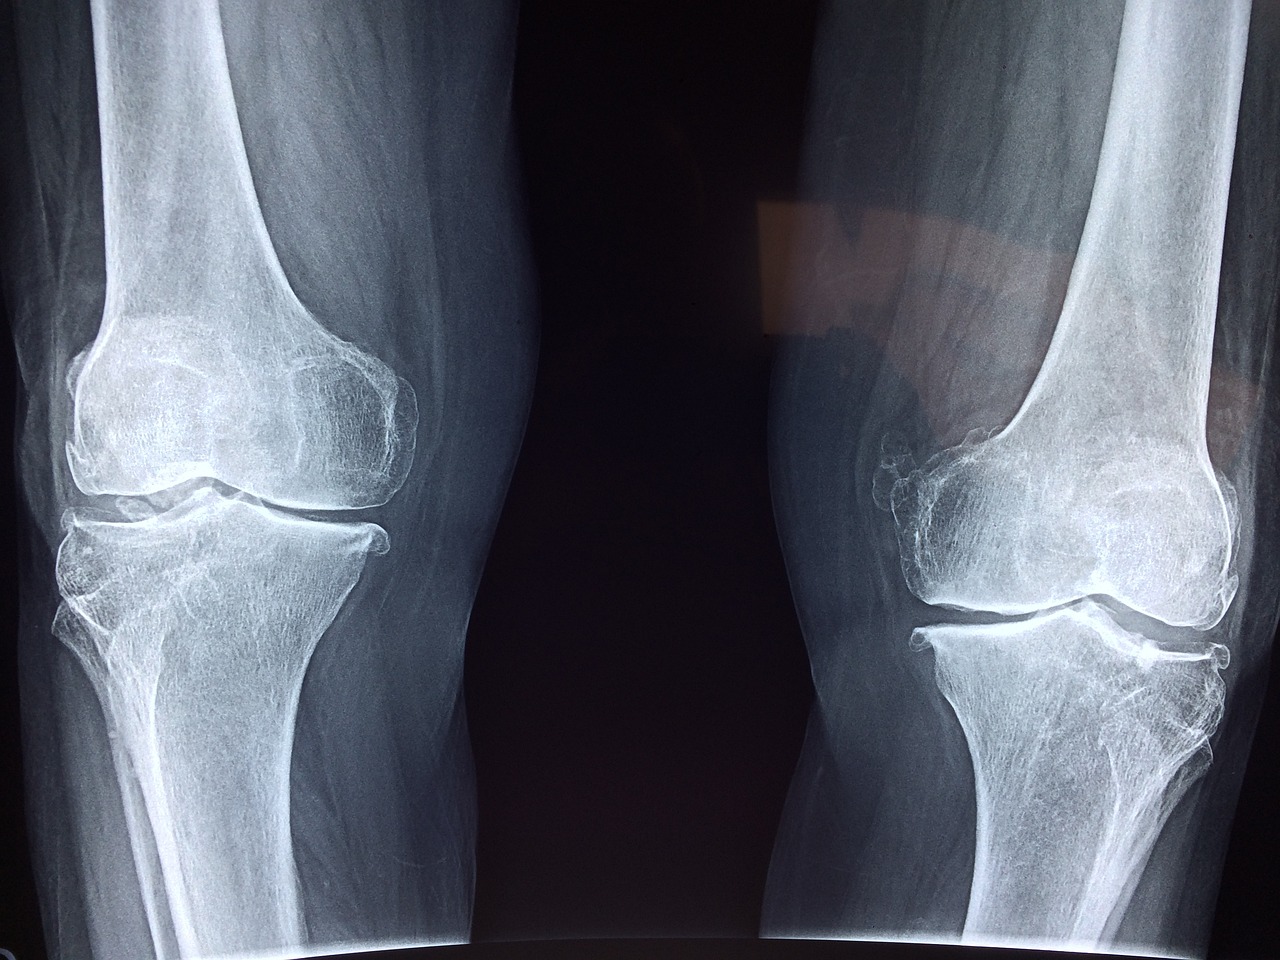

특히 연골이 닳기 시작한 50대 이상이나 퇴행성관절염 초기 증상이 있는 분들에게는 무릎에 체중이 실리는 동작은 오히려 부담이 될 수 있습니다.

무릎은 한 번 손상되면 회복이 어렵기 때문에, 지금부터 지키는 게 가장 좋은 방법입니다.